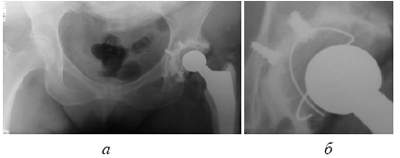

Рис. 5. Использование позиционирующих винтов (случай 1): а. тотальное цементное эндопротезирование левого ТБС, б. тот же снимок в увеличении - позиционирующие винты в дне впадины

впадины коротких кортикальных винтов (рис. 4). После обработки римированием внутрисуставного хряща, производится пробная установка кубка во впадине, при этом намечаются места установки позиционирующих винтов. После их установки кубок опять «вхолостую» устанавливается во впадине и кручением винтов (завинчивание или развинчивание) кубок позиционируется в оптимальную для имплантации позицию. Далее следует заливка цемента и стандартное закрепление ацетабулярного кубка, позиционирующие винты исключают возможность ошибки и децентрации.

Тем самым решается ряд важных проблем во время цементировки ацетабулярного кубка эндопротеза. Во-первых, оставшиеся вне кости головки винтов обеспечивают равномерное пространство для цементной мантии. Во-вторых, их высота, достигаемая завинчиванием или развинчиванием, по разному упираясь в кубок, позиционирует его, чем исключается возможность децентрации или изменения угла во время цементировки. И наконец, имплантированные винты создают дополнительную фиксацию и, наряду с отверстиями в дне вертлужной впадины, увеличивают контактную поверхность с цементом (рис. 5и6).